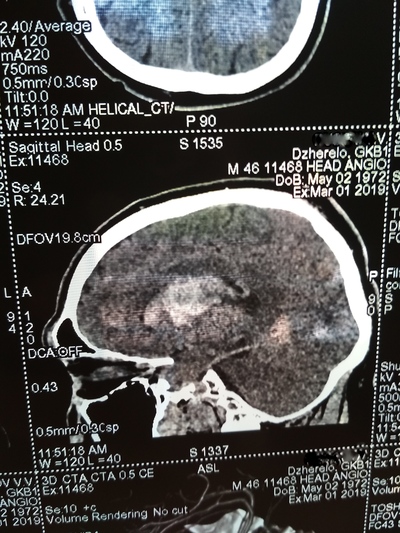

День не помню, возможно 1-2 марта, открываю глаза, а вокруг суета и непонятная обстановка. Осознаю что я а больнице, меня перетягивают с кровати на носилки и куда-то катят и тащат, укрыли сверху одеялом, внесли на улицу, очень холодно. Притащили (по другому не назовешь) меня на компьютерную томографию, перекинули с носилок на стол КТ, голову уложили в ячейку для головы и чем-то расклинили, чтобы не шевелился, больно капец. Я уже осознал что нахожусь в больнице, но что произошло не могу понять, да и думать мне было очень больно в голове.

Вернули меня в палату, перекинули на койку, и мои родные начали рассказывать, что 22 февраля мне стало плохо, качало, тошнило и рвало, жена подумала, что я выпил с друзьями в гараже. Потом вызвали скорую, которая померяла давление и там 290 на 160. Что то укололи. Потом возили в одну в больницу, они отказались принимать, повезли в другую. Вот так с 26 февраля я оказался в "еврейской", это у нас так называют гкб1. (городская клиническая больница № 1) По компьютерной томограмме врач определил геморрагический инсульт и аневризма, вот описание что это такое:

Пример аневризмы сосудов головного мозга

После КТ со мной общался врач, видя, что я уже в сознании, трогал руки ноги, просил потянуть рукой его руку, у меня плохо слушалась правая сторона тела.

Ещё врач сказал что желудочки головного мозга заполнились вытекшей кровью и они решают или вскрывать черепушку или медикаментозно лечить.

Вот тут я пересрал, совершенно не хотел проветривать бестолковку (но обрадовался когда на снимках всё таки обнаружили мозг 😁)